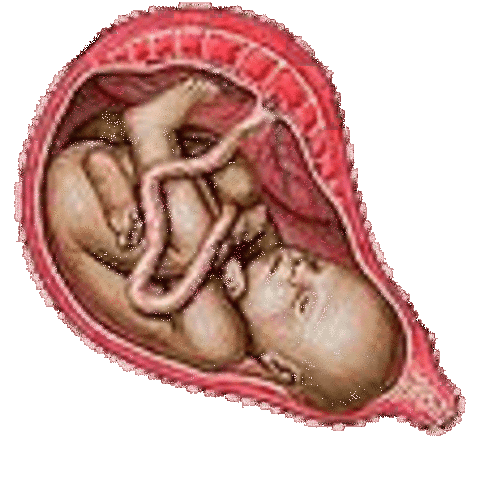

• Week 36

Week 36

The baby is very chubby now due to the fat layers. The baby dropped into the birth canal and is ready for birth.